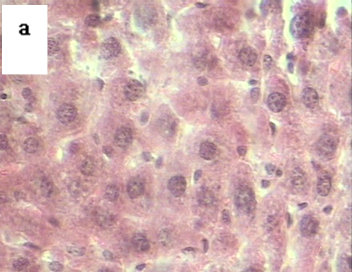

Liver tissues of DBN treated mice, and normal control age-matched mice were examined microscopically at a magnification of 40x (fig. 3). Significant morphological changes were seen in the liver cells following DBN treatment upon comparison with age-matched normal control mice. When compared liver tissues cells of control mice were found to be in regular morphology, cell to cell contact was seen. Hepatocytes in normal mice had well-defined outlines with mono and bi-nucleated cells. In the cell of the liver tissues of treated mice no regular morphology was seen, cells showed variations in shape and size. Loss of cell to cell contact. Most of them were seen having an irregular outline and to be multinucleated.

Fig. 3: Microphotographs of the histological section at 40x of liver from (a) normal control mice and (b) N-Nitrosodibutylamine (DBN) treated mice showing distorted and multinucleated cells. The slides were stained with hematoxylin and eosin. Slides were examined microscopically after drying

Histological studies were done for the verification and for monitoring the success of cancer induction. Many changes were observed when the histological liver sections from treated and normal were compared. Liver cells in DBN treated mice were found with poorly defined cell boundaries, irregularity in sizes and shapes, the absence of a cell to cell contact. Most of the cells were found to be multinucleated, and nuclei appeared to be more densely stained which may be due to condensed chromatin. Whereas the liver cells of normal mice did not show any such changes and most of the cell had well-defined morphology and found to be single or binucleated (fig. 3). The observed morphological changes further indicated that cells are in a state of rapid division, loss of functions and supported the progression of cancer induction.